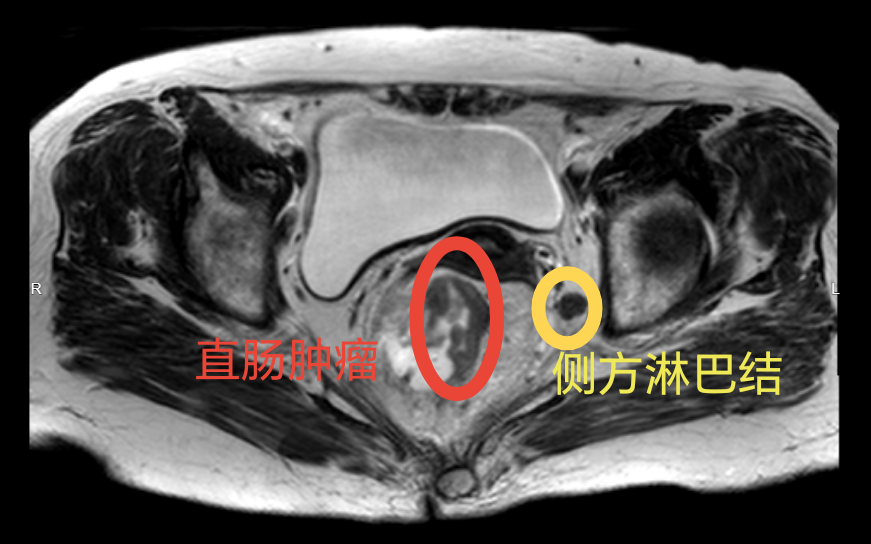

侧方淋巴结,就位于盆腔两侧的深部,如同树木深埋在土壤里的侧根。在部分进展期直肠癌,尤其是位置较低的直肠癌患者中,癌细胞有可能沿着这条“侧方通路”进行转移。

1、术前高分辨率MRI(磁共振)提示侧方淋巴结可疑转移的患者;